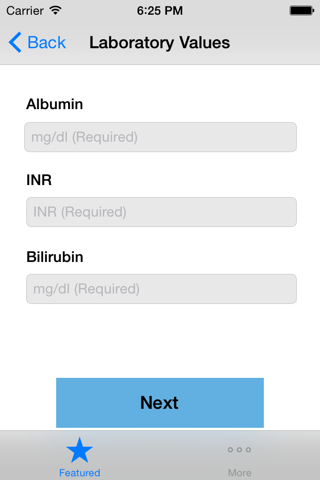

Child-Pugh (CP) classification was originally designed to determine the risk of portocaval shunt surgery in cirrhotic patients. CP classification provides mortality risk with abdominal surgery, survival rates and a likelihood of developing complications secondary to underlying cirrhosis. The input variables include serum bilirubin, serum albumin, presence of ascites or encephalopathy and prothrombin time. The minimum CP score is 5 whereas the maximum possible score is 15. A score of 5-6 is classified as class A indicating well compensated cirrhosis, whereas a score of 7-9 is class B with significant functional compromise, and a score of 10-15 is a class C with decompensated cirrhosis. This application implements the CP classification system and assigns a score and stage based on the user provided input.